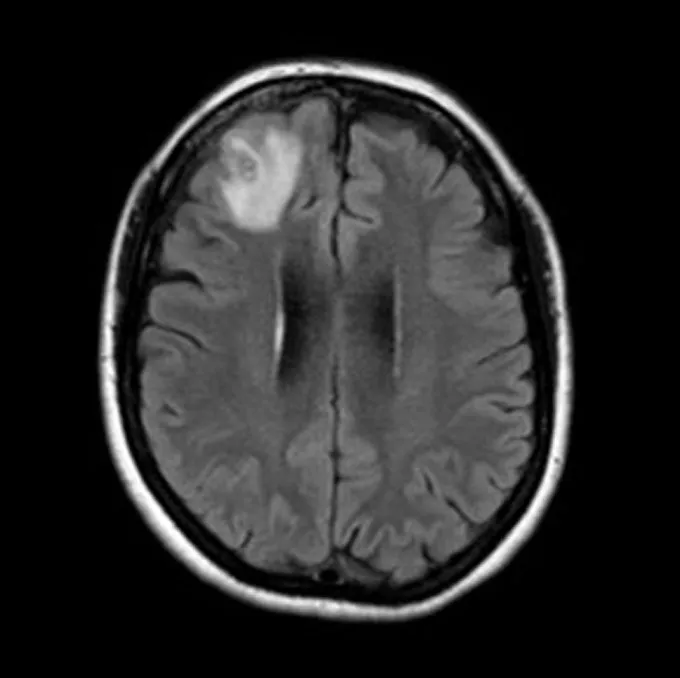

腦部掃描顯示,她的額葉發出幽靈般的光芒。醫生認為這可能是癌症、膿腫或其他疾病,「沒有人認為它會是一隻蟲。」

醫生決定對大腦進行活組織檢查時,發現了一個可疑的繩狀結構,並用鑷子將其拔出,「它是粉紅色的,大約有鉛筆一半長,而且還活著。」